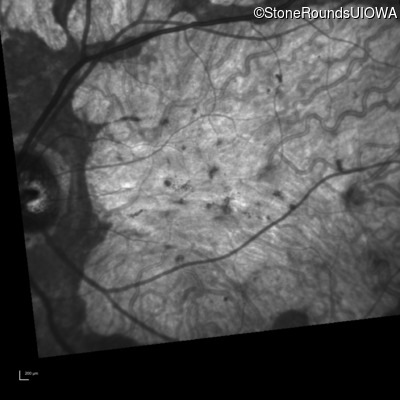

Infrared Fundus Photograph - Left - 20/200 +1 sc

Exemplar

Infrared Fundus Photograph - Left - 10/125 +1 sc